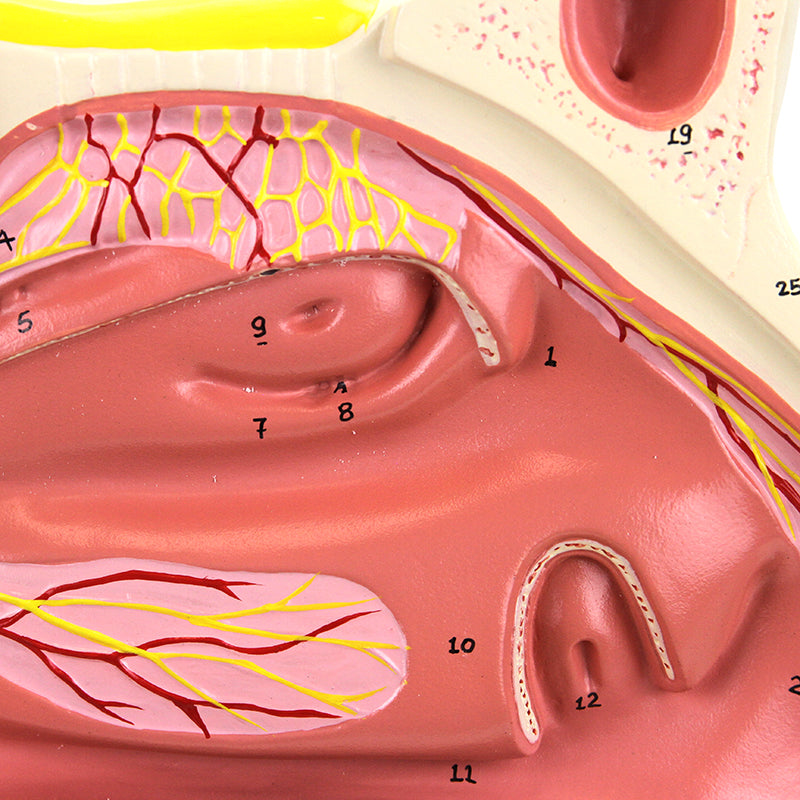

鼻腔模型,放大三倍,三部分組成

此模型為實物三倍大小,展示鼻腔的中間剖面。鼻中隔及部分嗅覺上皮可拆卸,以顯示深層內部結構。重要解剖結構均有編號;採用耐用合成材料製成。配合擴增實境的互動式三維解剖模型,是促進學習與輔助教學的絕佳工具。此平台讓學生能進行解剖模型的比較分析,對比各器官的結構差異。此計畫亦提供持續教育的平台,為所有學生提供機會,增進對解剖學、生理學及病理生理學的認識。

鼻腔模型,放大三倍,三部分組成

此模型為實物三倍大小,展示鼻腔的中間剖面。鼻中隔及部分嗅覺上皮可拆卸,以顯示深層內部結構。重要解剖結構均有編號;採用耐用合成材料製成。配合擴增實境的互動式三維解剖模型,是促進學習與輔助教學的絕佳工具。此平台讓學生能進行解剖模型的比較分析,對比各器官的結構差異。此計畫亦提供持續教育的平台,為所有學生提供機會,增進對解剖學、生理學及病理生理學的認識。